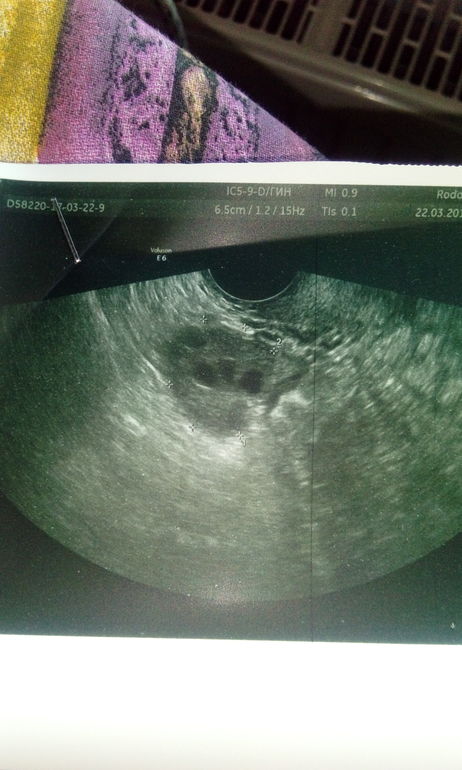

Посмотрите УЗИ

ФолликулометрияДелала на 9 день цикла. Обычно цикл 33 дня( может и больше до 35), но чтоб 26 дней ( как в этот раз)для меня это нонсенс. В итоге гормоны 2 фазы получилось неправильно сдала, что так рано дела начались и шли 7 дней, обычно 3-4 и свободна. Я так понимаю эндометрий совсем никакой и яичники МФя, да?